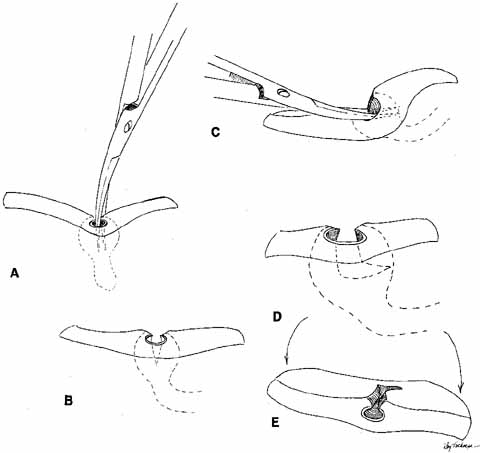

Many methods have been devised in an attempt to improve the original grooved

director retrieval method of Quickert and Dryden.63 A straight hemostat often can be used successfully in a larger child, particularly

when the turbinate is infractured. However, the malleable

Crawford-type probes offer an advantage in that they can be retrieved, even

in a small infant, by using the corresponding hook Fig. 24).64,74 It is important to recall the intranasal anatomy while retrieving the

malleable probe. The nasal floor, which is also the palate, is the inferior

limit of the inferior meatus. The inferior turbinate arises from

the lateral nasal wall. Thus, by staying parallel to the palate and directing

the hook laterally towards the ear, the inferior meatus is easily

located. After entering the inferior meatus, tactile movement is

required to locate and retrieve the Crawford probe. Detachment of the

Silastic from the probe may occur when the probe is retrieved from the

inferior meatus of the nose and the junction of the tubing and the probe

is pulled through the punctum into the nasolacrimal system. Usually, dilation

of the punctum before insertion of the probe and application

of an ointment for lubrication at the junction of the metal and Silastic

will prevent this detachment.  Fig. 24 Crawford probe insertion and removal with a crochet-type hook. Fig. 24 Crawford probe insertion and removal with a crochet-type hook.